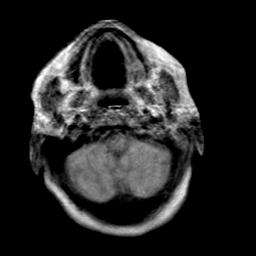

Creutzfeld-Jakob disease: proton density-weighted MR -- Slice #2

[Home][Help][Clinical] Slice 2